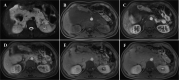

Intra-abdominal venous malformations and inferior vena cava aneurysms are rare and difficult to diagnose because of their nonspecific clinical symptoms. These vascular anomalies are important entities due to the risk of thrombosis or rupture. According to the classification of International Society for the Study of Vascular Anomalies, venous malformations are classified as low-flow vascular anomalies, showing absence of arterial and early venous enhancement and slow gradual filling with contrast on delayed venous imaging. Phleboliths related to thrombosis and calcifications, are the key finding of venous malformations. In this article, we report an exceptional case of large intra-abdominal venous malformations in associated with an inferior vena cava aneurysm.